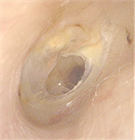

1. 慢性中耳炎の定義:鼓膜穿孔が3か月以上持続し、耳漏を繰り返す中耳の慢性炎症性疾患を指す。世界的には中耳真珠腫を含む概念であることに留意する(推奨度1、RJ)

1. 診断の基本:鼓膜所見による診断が基本であり、必要に応じて側頭骨CTで含気化や陰影を確認する。中耳真珠腫疑い例ではMRIが有用である(推奨度1、RJ)